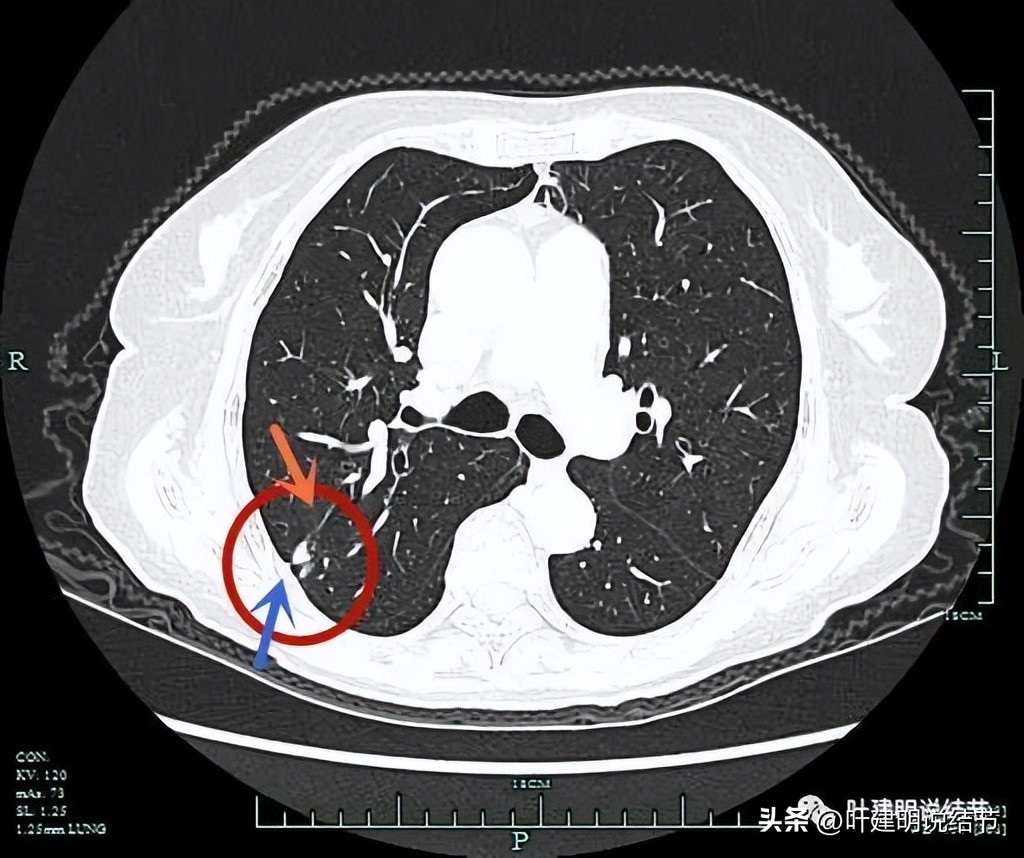

微小血管进入(桔色箭头),胸膜略有牵拉(蓝色箭头)。